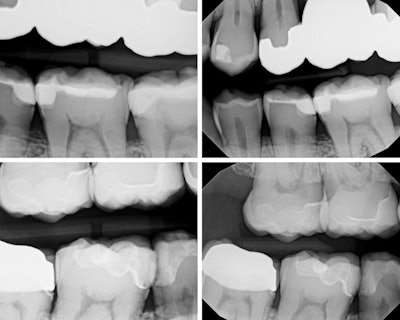

In my own practice, I compared two bitewings from the same patient, one taken with Acuity and one with our existing sensor, using identical exposure settings. The Acuity image immediately stood out. It showed noticeably sharper definition, cleaner contrast, and clearer interproximal visibility. The improvement was visible at a glance and reinforced the diagnostic advantages reported by our evaluators. This kind of image sharpness saves time and reduces retakes.

Figure 1: Four bitewings taken using the Acuity DXPD intraoral sensor.Dr. Chris Catalano.